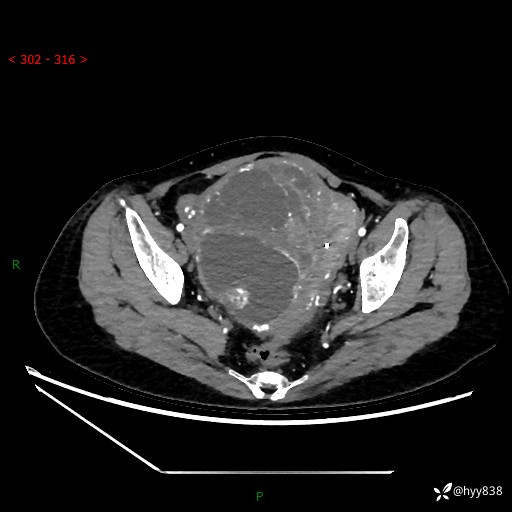

辅助检查:CT

盆腔CT平扫

增强(动脉期+静脉期)